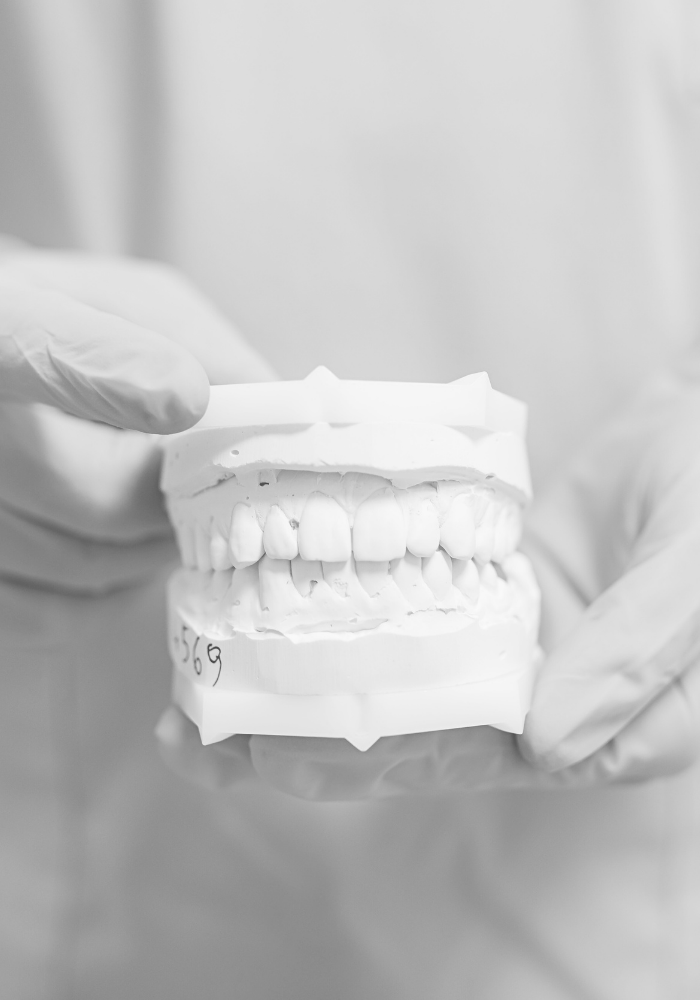

W estetycznej protetyce wax-up i mock-up to dwa etapy planowania i wizualizacji efektu końcowego:

- Wax-up to modelowanie nowego kształtu zębów z wosku na gipsowym odlewie Twoich zębów.

- Pozwala dokładnie zaplanować kształt, wysokość i proporcje przyszłych koron, licówek czy mostów.

- Protetyk może skorygować wygląd zębów zanim cokolwiek zostanie wykonane w ustach.